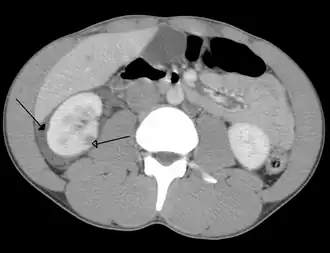

| Trauma abdominal resultando em uma contusão no rim direito (seta aberta) e sangue ao redor do rim (seta fechada), conforme visto em tomografia computadorizada. | |

Os rins também podem ser lesionados; eles são parcialmente, mas não completamente, protegidos pelas costelas.[6] Lacerações e contusões renais também podem ocorrer.[11] Lesões renais, um achado comum em crianças com trauma abdominal contuso, podem estar associadas a sangue na urina.[10] Lacerações renais podem estar associadas a urinoma ou vazamento de urina para o abdômen.[4] Um rim fragmentado é aquele com múltiplas lacerações e uma fragmentação associada do tecido renal.[4]